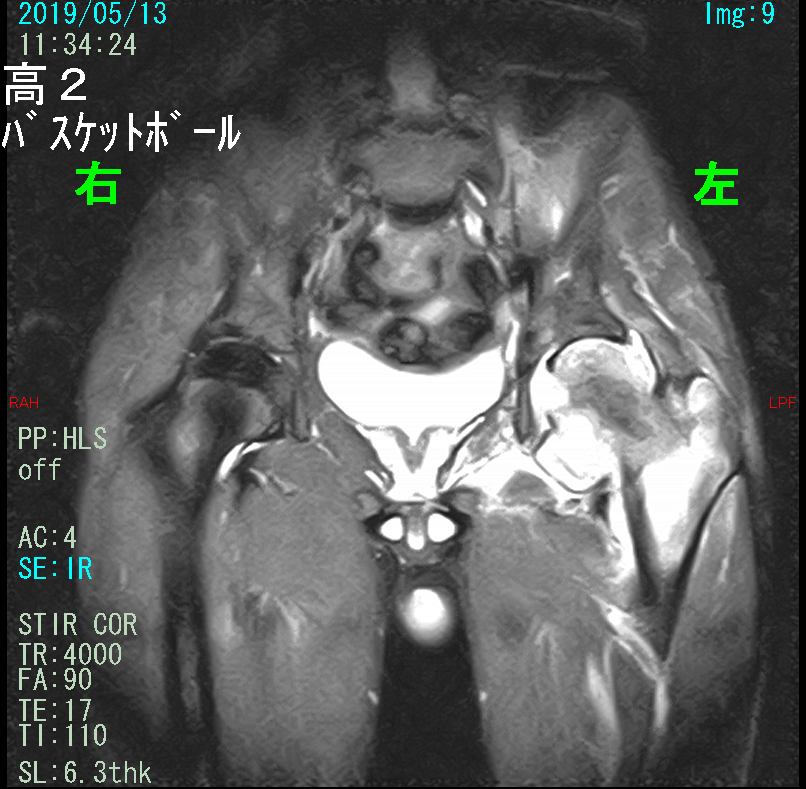

患者さんは16才の高校2年生のバスケットボール部の男子生徒です。令和1年5月13日に左股関節痛で当院を受診されました。2月半ばから左股関節痛があり、近くの整形外科にかかっていたけれど、良くならずバスケットボールができず、チームメートの友人に長沢先生の医院を受診した方が良いというアドバイスがあり受診されたのでした。この経過を確認しただけで、私は「やばい」と心臓が脈打つことを感じました。16才の男子生徒が股関節痛を発症したとしても、それは何らかの股関節に起因するスポーツ障害か、腰のヘルニアの坐骨神経痛の症状であり、どちらにしても1か月もスポーツを休んでいれば自然経過で良くなり早く練習したいとなるはずだからです。あまりに早く練習を再開すると症状が再発する場合もあるかもしれませんが、K君の場合はそのような経過ではありません。3か月も部活を休んでいるのに股関節痛が軽減していかないのです。整形外科医なら「これはおかしい」と感じて当然なのです。私は何か悪い病因があって改善傾向となっていない可能性が高いと感じました。K君の症状の改善しない経過に何の関心も示さずに、ただただ漫然と3か月も鎮痛薬を処方している整形外科開業医は整形外科医療を行おうとしているのではなく、単にお金がほしいだけの整形外科というお店を出しているのだと確信します。

16才男 MR1.jpg

MRI検査(STIR条件)では本来骨は右股関節のように黒っぽく描出されるのですが、左の股関節・大腿骨は真っ白に描出されました。これは骨が損傷して出血している所見です。16才の男の子で見たことない状態でした。